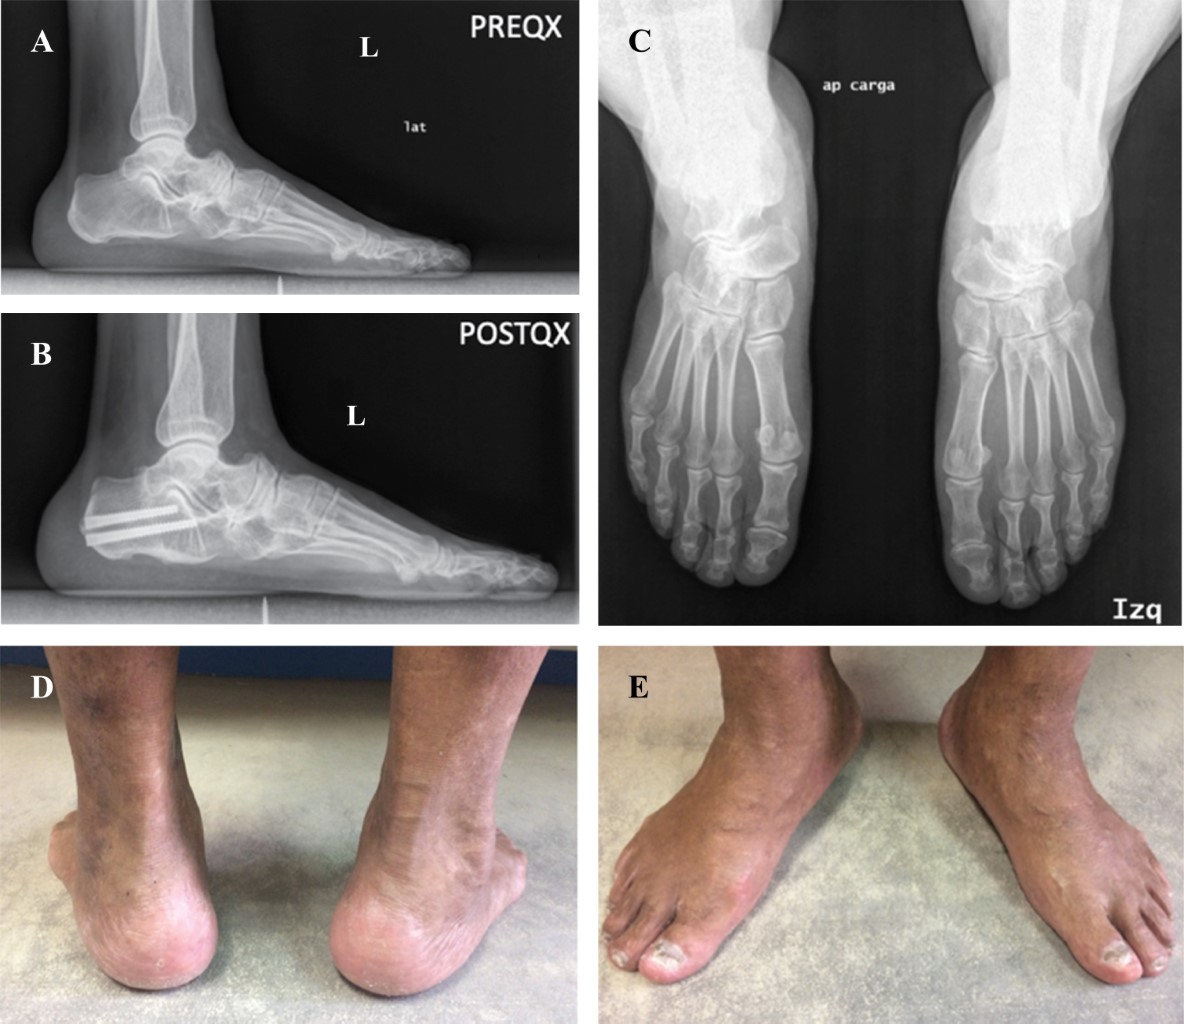

Lateral osteotomy of the calcaneus in the treatment of Müller-Weiss disease

Introduction: The deforming condition of the navicular bone known as Müller-Weiss disease (MWD) is a rare disease. Patients present with chronic pain in the talonavicular joint and a paradoxical flat foot with a varo hindfoot. Objective: To analyze the clinical results of a lateral osteotomy of calcaneus applied to patients with MWD. Material and methods: Retrospective observational study carried out in two hospitals. The series consists of nine cases in eight patients, all of them with symptomatic Müller-Weiss disease, treated by lateral osteotomy of the calcaneus between 2012 and 2017, obtaining an average follow-up of 4 years (2-6). The mean age was 62 years (50-75). In all patients, Costa-Bartani angles (CB), Kite angle and Calcaneal Inclination (CI) were measured. In addition, the Manchester Oxford Scale (MO) to measure the post-surgical satisfaction of patients. Results: All patients report having improved their pain by obtaining a postoperative score on the mean Manchester Oxford scale of 32.54 points (15.62-53.75). In 66% of patients the CB angle improves, the Kite angle in 89% and the CI in 33%. Conclusion: The improvement in the pain of the patients in our series is not accompanied by radiological changes in the same proportion, it is a simple and uncomplicated technique in our follow-up.

Figure 1